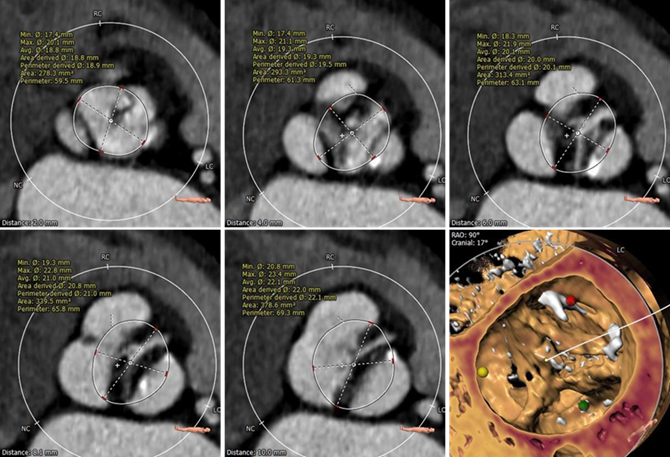

主动脉根部评估

Type1型二叶瓣,右无冠窦发育不全,交界处形成非钙化嵴,伴有瓣叶严重纤维增厚。

右冠高度11.8mm,左冠高度19.3mm,双侧瓣叶长度小于瓣叶附着缘到冠脉开口距离,冠脉遮挡风险较小。

主动脉瓣环与水平面夹角77°,呈横位心。

瓣环上解剖评估

瓣环上轻度钙化,瓣叶纤维增厚明显,瓣上最狭窄处周长:59.5mm,直径:18.8mm。